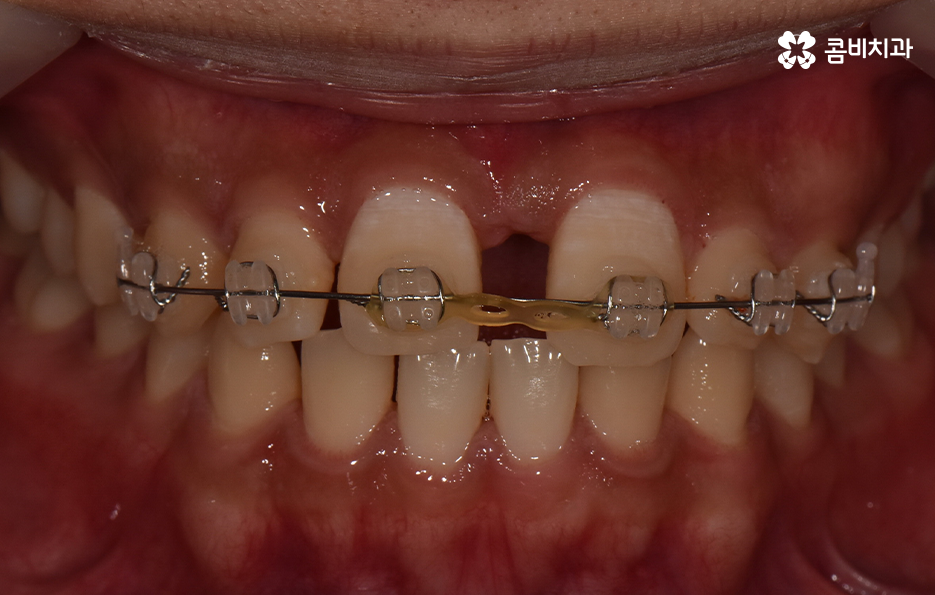

치아교정 기간은 각 환자분들에 따라 천차만별이기 때문에 정확하게는 각 환자분들의 상태를 직접 확인해봐야 하며 누구나 앞니만 부분적으로 교정이 가능한 것은 아니기 때문에 정밀검진이 우선적으로 필요하며 위 환자분의 경우에는 과잉치를 발치하고 교정기 장착 후에 약 6개월 정도가 지나서 교정기를 떼어낼 수 있었어요

앞서 말씀드린 것처럼 치열 전체로 보자면 전체교정을 통해 보다 심미적이고 치아의 건강, 기능적인 부분을 좀더 개선할수도 있었겠지만 오랫동안 앞니로 인해 콤플렉스를 갖고 지내다보면 앞니만이라도 빠르게 결과를 얻고 싶어 하는 환자분의 니즈도 있게 되고 전체교정을 하면 그에 따른 교정 기간과 비용적인 부분도 크게 증가하기 때문에 앞니 위주로 교정을 한 사례라고 보면 좋을 거예요